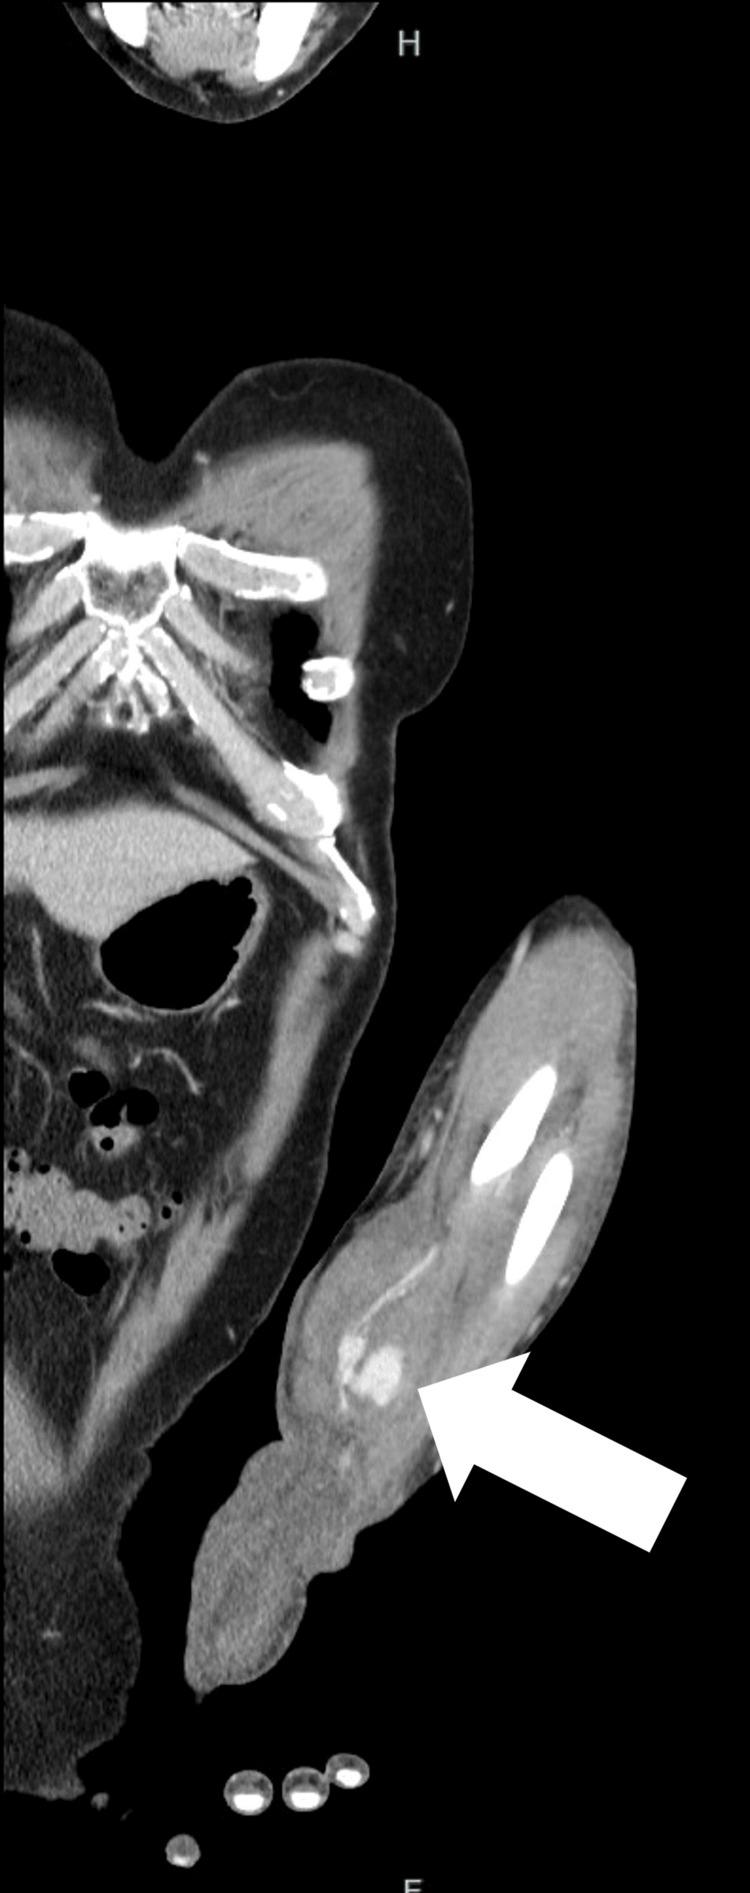

Pseudoaneurysms of the radial artery often occur in association with catheterization procedures or trauma, and idiopathic cases are rare. Point-of-care ultrasonography (POCUS) is effective for diagnosis; however, the effectiveness of endovascular treatment for pseudoaneurysms remains unclear. A 64-year-old male patient presented to the emergency department with pain and swelling of the left forearm and hand. Symptoms appeared seven days prior and were treated with antibiotics, but there was no improvement. POCUS revealed a yin-yang sign, and contrast-enhanced computed tomography revealed a pseudoaneurysm of the radial artery. Endovascular treatment was performed. Idiopathic radial artery pseudoaneurysms are rare, and differentiating them from other soft tissue diseases is important. Emergency physicians should be aware that POCUS is effective for the rapid diagnosis of idiopathic radial artery pseudoaneurysms and that endovascular treatment is less invasive and may be effective.

桡动脉假性动脉瘤常与导管插入术或外伤相关,特发性病例罕见。床旁超声检查(POCUS)对诊断有效;然而,血管内治疗假性动脉瘤的有效性仍不明确。一名64岁男性患者因左前臂和手部疼痛肿胀就诊于急诊科。症状于7天前出现,曾接受抗生素治疗,但无改善。POCUS显示阴阳征,增强计算机断层扫描显示桡动脉假性动脉瘤。遂进行了血管内治疗。特发性桡动脉假性动脉瘤罕见,将其与其他软组织疾病相鉴别很重要。急诊医生应意识到POCUS对快速诊断特发性桡动脉假性动脉瘤有效,且血管内治疗侵入性较小且可能有效。